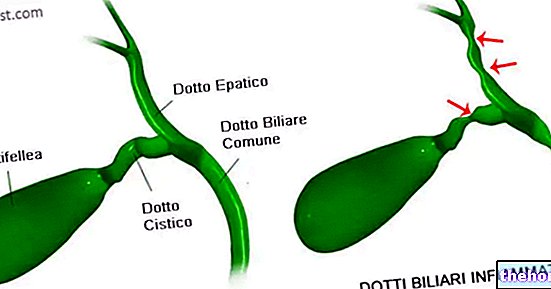

Фотографии и изображения, связанные с симптомами первичного склерозирующего холангита